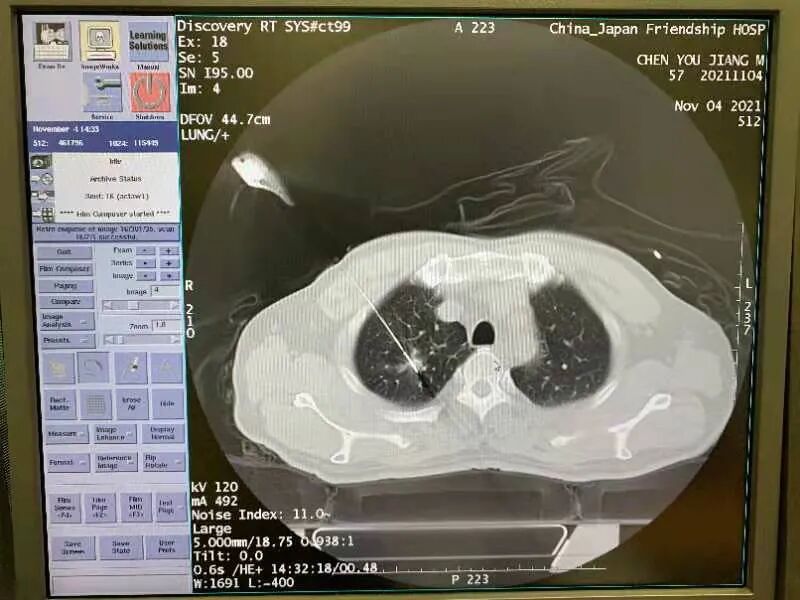

经介入医学科与肺癌病区杨萌副主任医师联合讨论后,患者入住肺癌病房并尽快完成各项术前检查工作,并对患者肺部情况进一步实施CT平扫加增强,进行评估。在对患者病情进行分析讨论和充分告知情况下,于11月4日下午对患者实施微创治疗。

本次手术在介入医学科新建综合手术室进行。介入医学科于明安主任团队实施完成,手术麻醉科张亚军副主任给予静脉镇静镇痛和术中保驾护航。在Angio-CT一体化介入平台CT影像的清晰精确引导下,通过精准穿刺和多点布针,成功对右肺上叶肺癌病灶进行扩大消融,消融时间约20分钟。术后进行穿刺活检以备病理学检查。手术过程顺利。